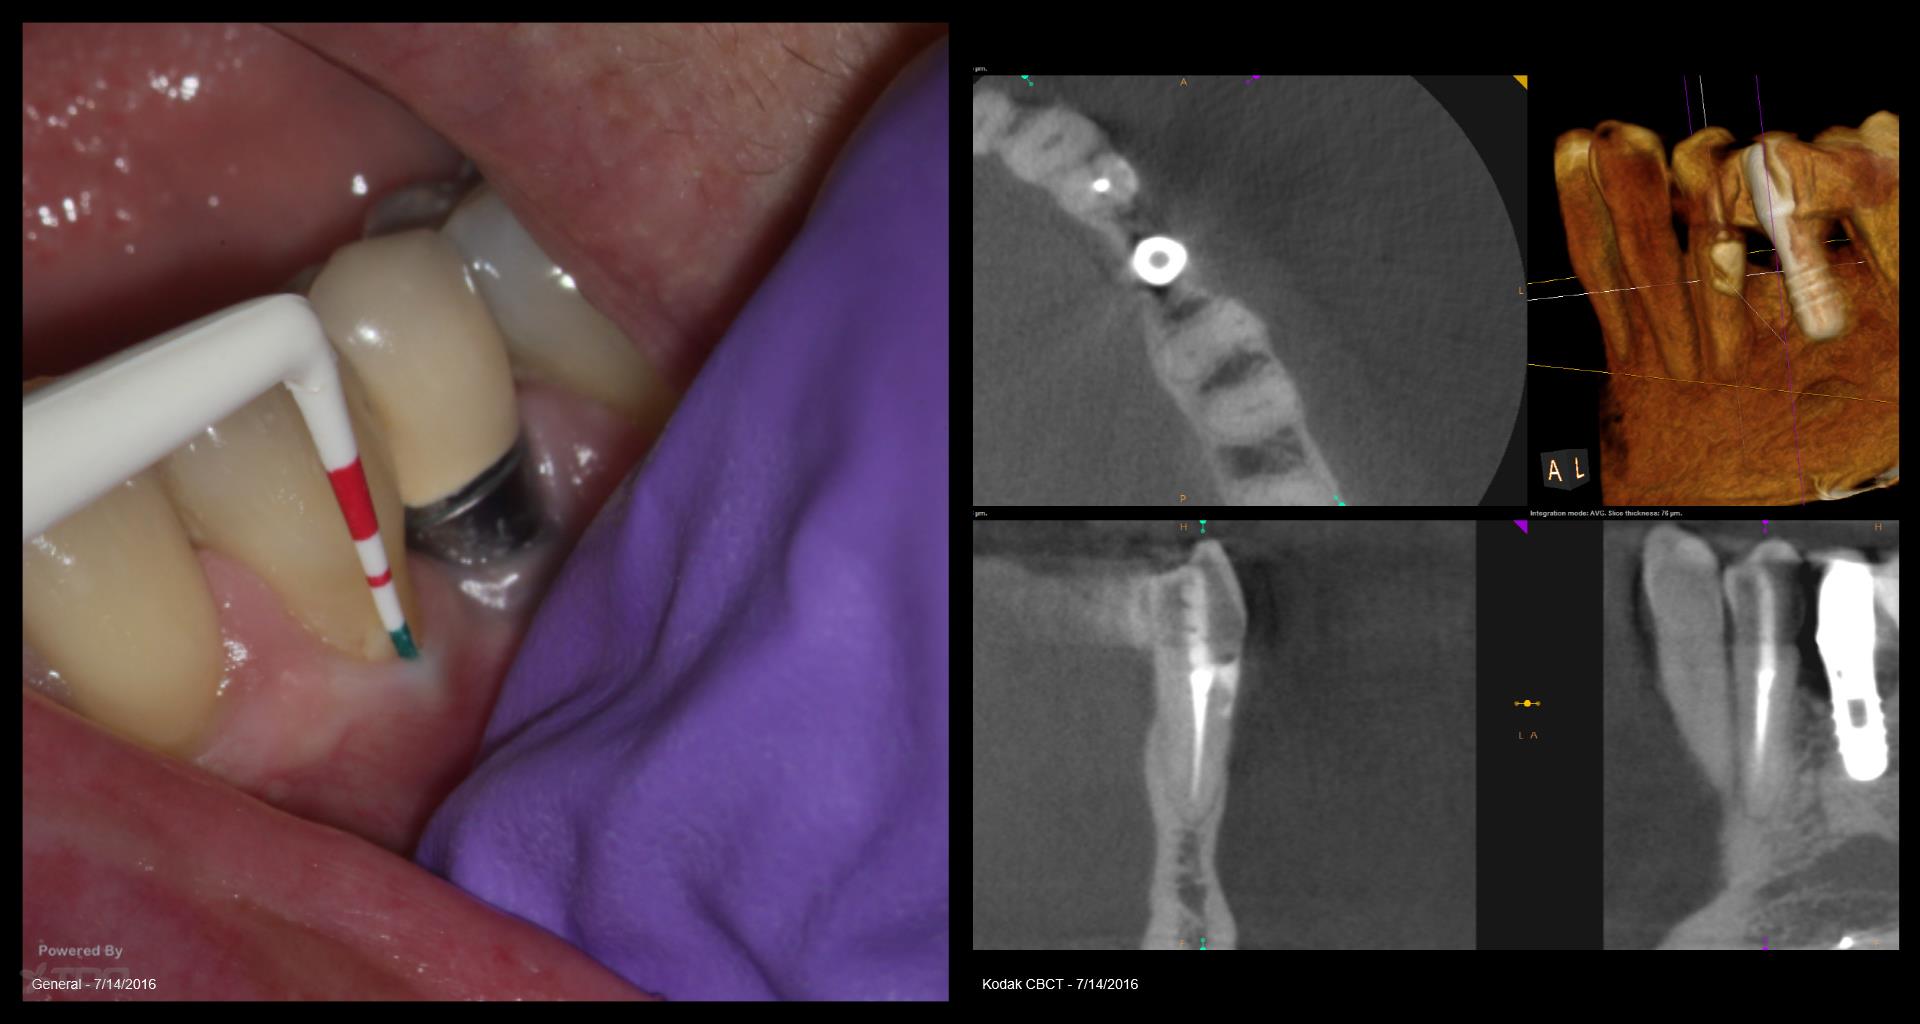

I struggled with the composite. I think I could do it better today but at least the repair seems to be holding. The defect went from line angle to line angle–the whole buccal face of the tooth. . gbc